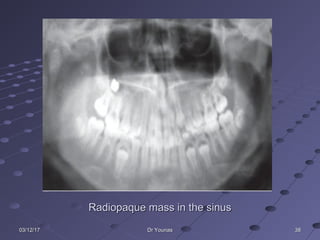

383803/12/1703/12/17 Dr YounasDr Younas

Radiopaque mass in the sinusRadiopaque mass in the sinus

383803/12/1703/12/17 Dr YounasDrYounas Radiopaque mass in the sinusRadiopaque mass in the sinus